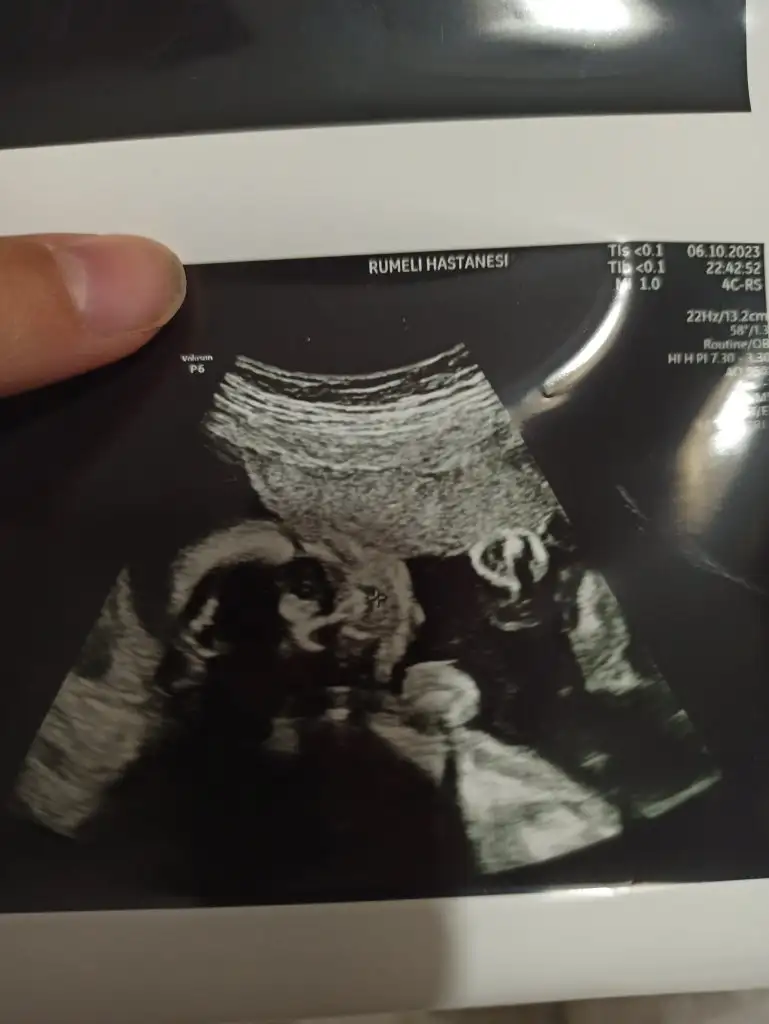

Kiz dedi doktorNeymiş cinsiyeti kuzunun

Sağlıkla gelsinBugün ki ultrason fotoğrafı